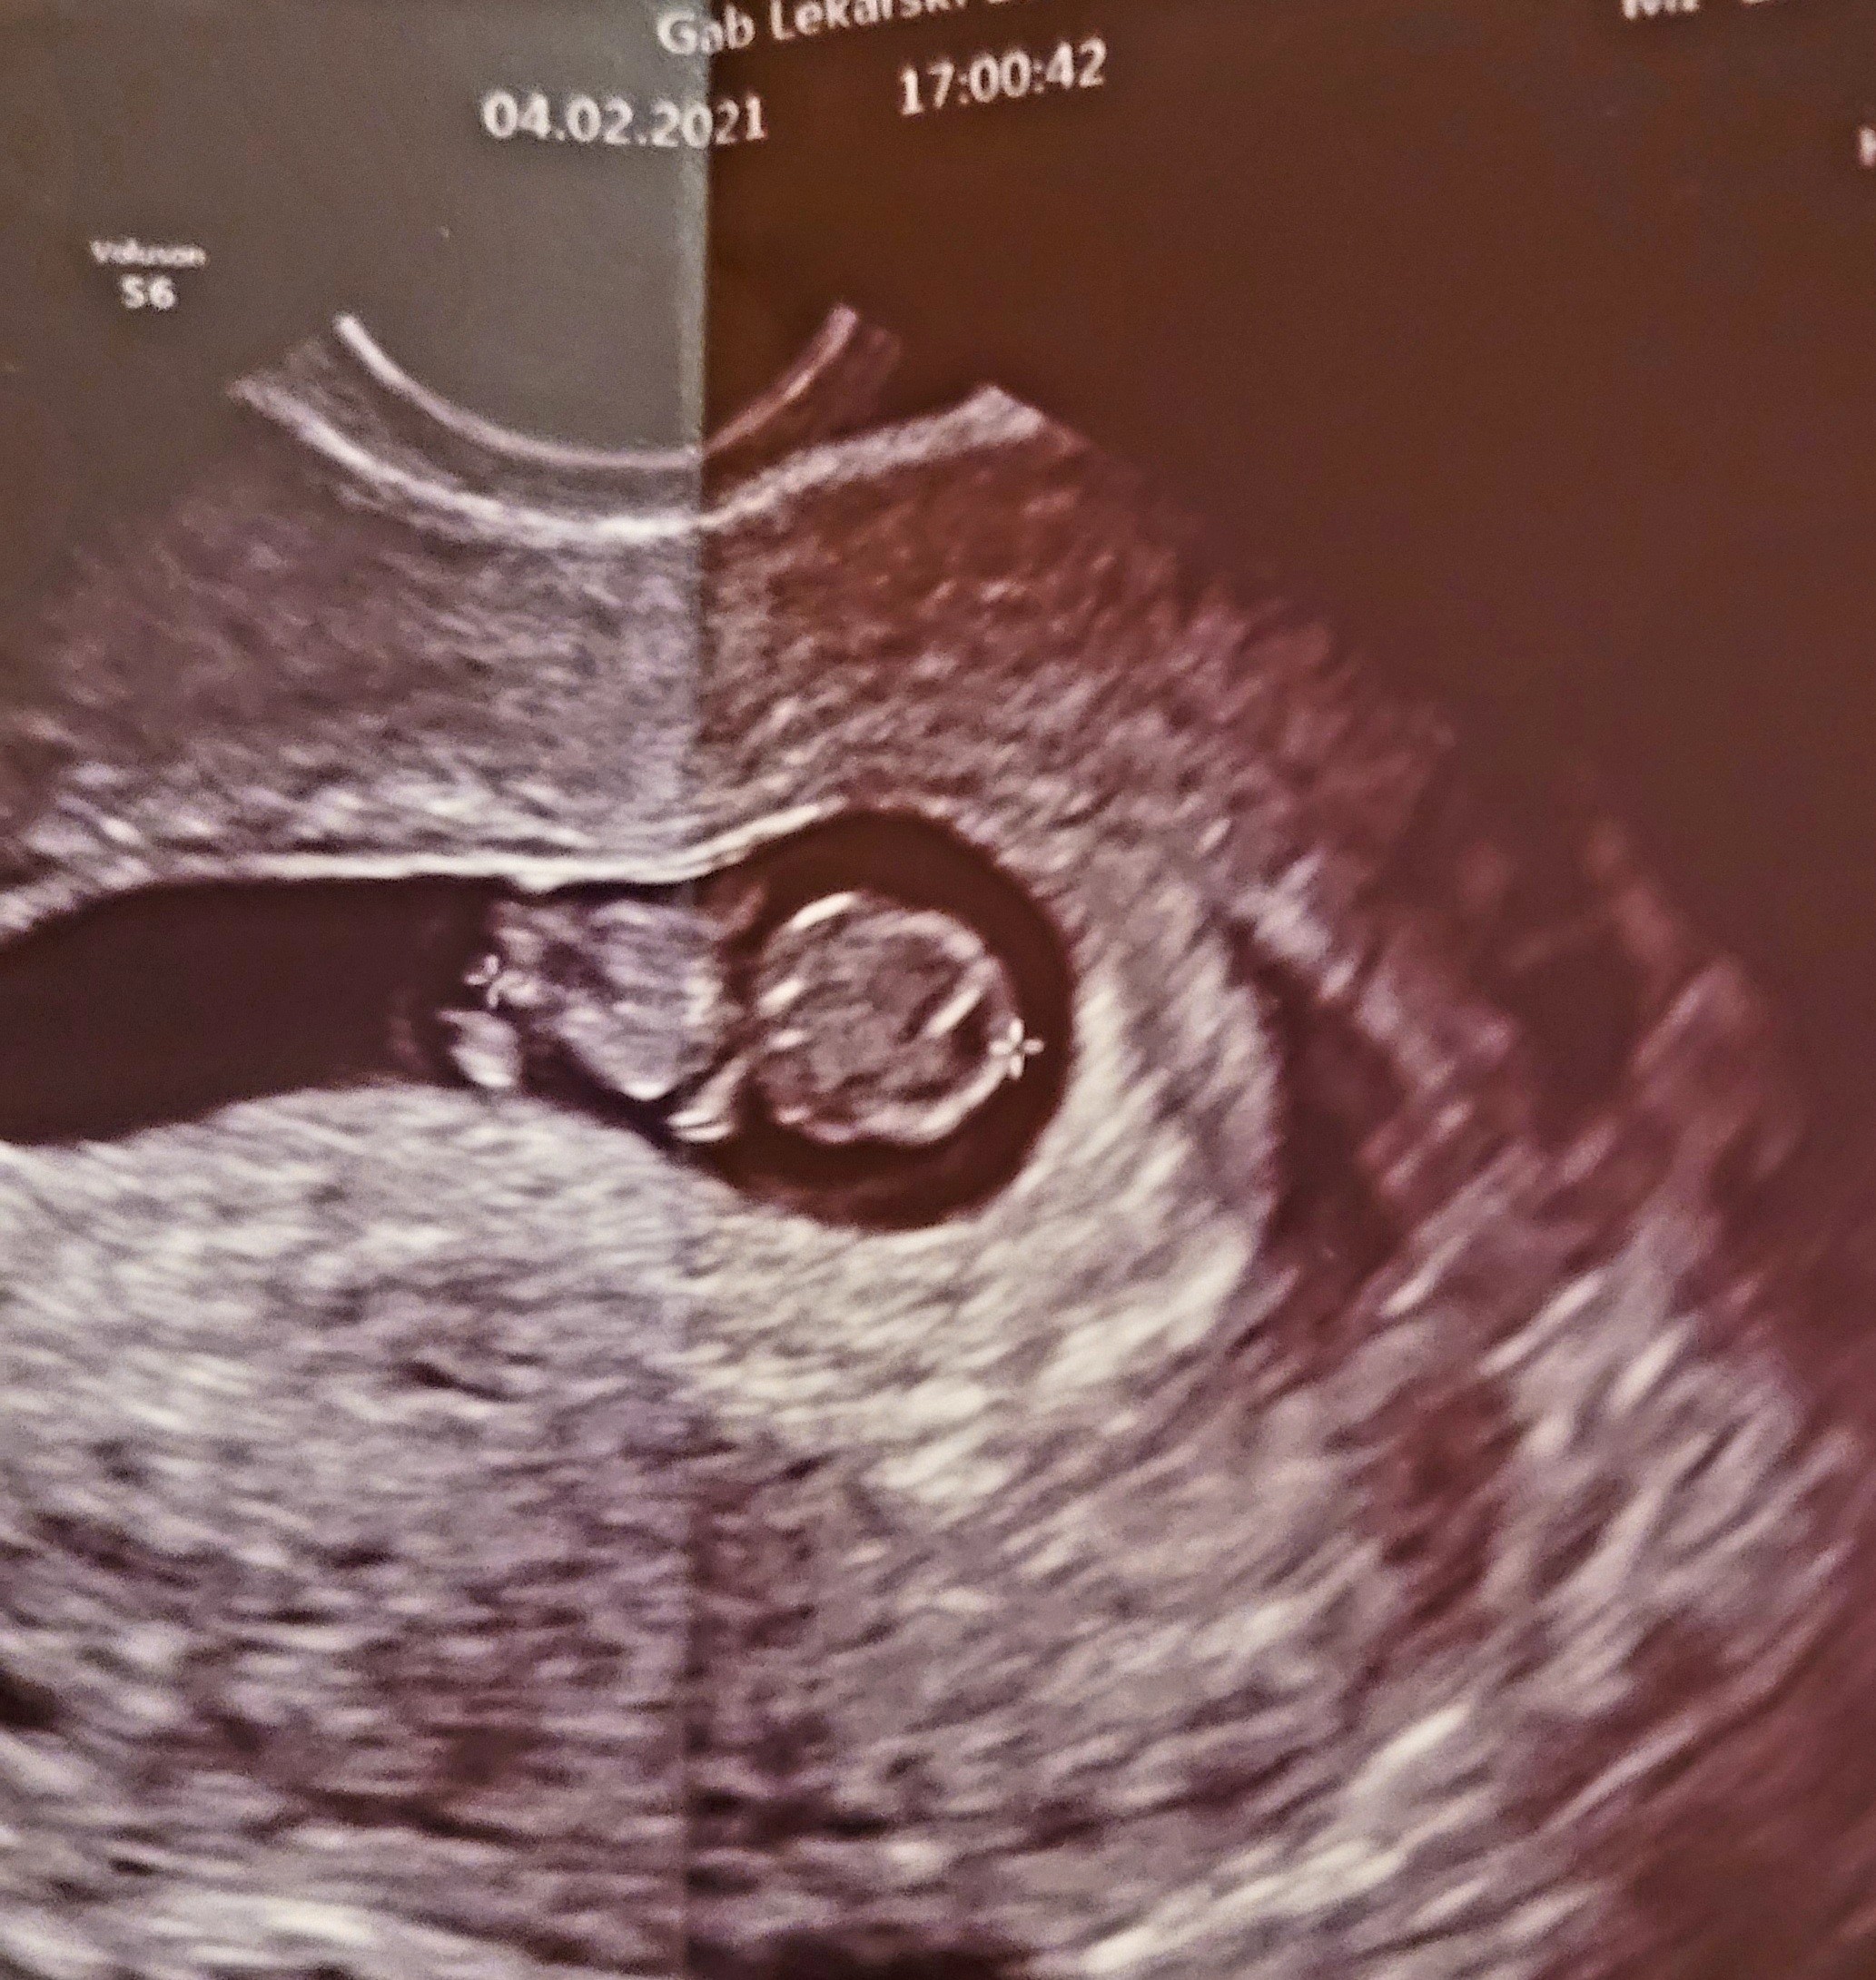

Hehe o proszę to się nazywa mieć szczęście [emoji846] super się złożyło [emoji16][emoji16][emoji16]Haha dobre jaja [emoji23][emoji23][emoji23] coś wam powiem... Tesciowie dziś kupili samochód... No i rozmawiają z tą kobietą od której odkupują i ona opowiada... Ze ona pracuje w kole łowieckim i zmienia samochód bo chce nowszy taki roczny (sprzedawała 5 latka)... No a teściowa zapytała a mąż, czym się zajmuje... A ona wie Pani mąż jest lekarzem. Moja teściowa zaintrygowana dopytuje jaka dziedzina... A ona ze ginekolog [emoji23] i że jakby trzeba było to jest ordynatorem na ginekologii w jednym ze szpitali u nas w mieście i żeby się powołać na samochód i coś będzie załatwiał [emoji23] dodatkowo prowadzi klinikę niepłodności [emoji23][emoji23][emoji23] także taki zbieg okoliczności [emoji23] a kobieta przecież nawet nie wiedziała że tesciowie spodziewają się wnuka [emoji23][emoji23][emoji23][emoji23]

I chyba wiem gdzie będę rodziła... [emoji23][emoji23][emoji23]